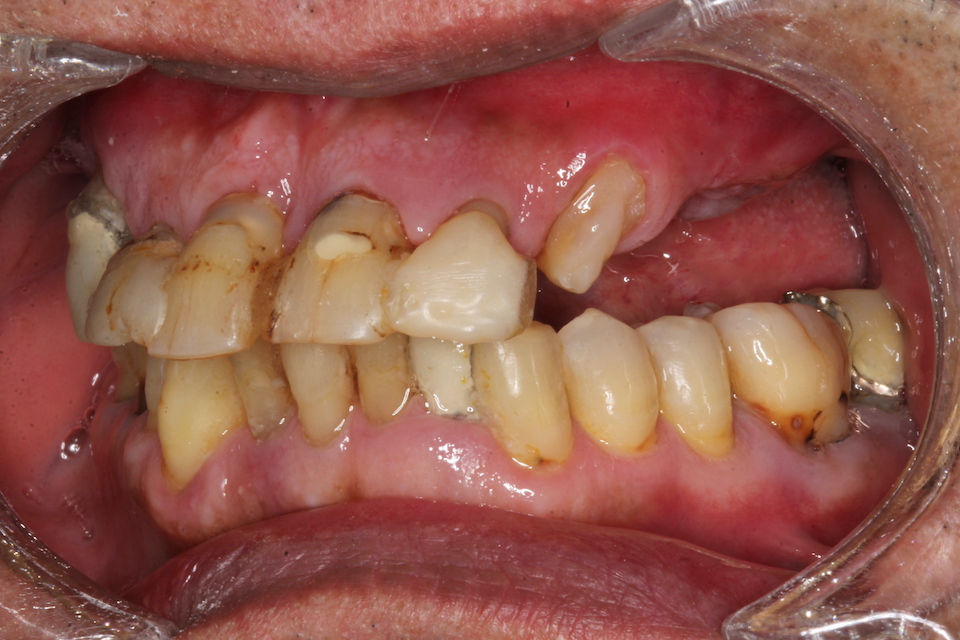

パッチン義歯2.1(削らないブリッジ) 2025.11.04

半口腔内製作義歯1.0 2025.06.24

半口腔内製作義歯0.6 2025.06.17